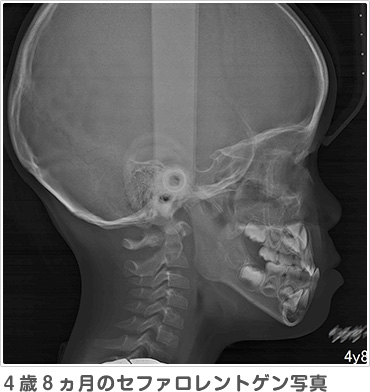

レントゲンは通常大きなレントゲンを2枚撮影します。パノラマレントゲンからは、おもに将来の永久歯の数が足りているか、永久歯の前歯はどのような形で生えてくるか、スペース不足はどのくらいか、などを予測します。セファロレントゲンからは、顔に対してアゴや歯並びがどのくらいの位置にあるのか、将来どのように成長する傾向があるのか、などを基準となる位置の角度を測って計測します。